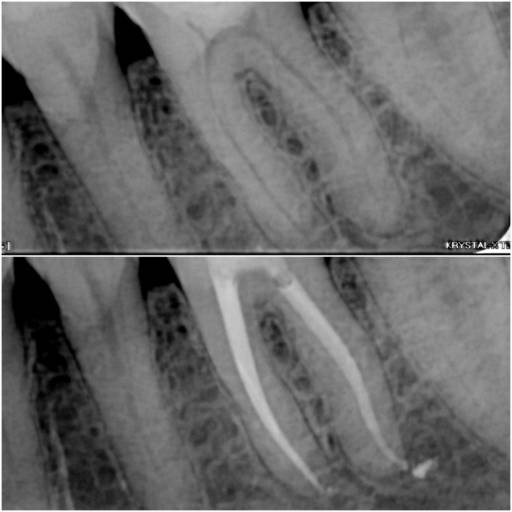

OdontologiaO tratamento endodôntico, popularmente conhecido como canal, é indicado para salvar dentes comprometidos por cáries profundas, fraturas ou infecções. Na Jardim Odontologia Clínica Integrada, em Francisco Beltrão – PR, o procedimento elimina a dor, trata a inflamação da polpa dental e preserva a estrutura natural do dente, evitando extrações desnecessárias.

O tratamento de canal é essencial quando o nervo do dente está comprometido. Com técnicas avançadas de instrumentação e obturação, garantimos eficácia, durabilidade e conforto durante todas as etapas. Em Francisco Beltrão, a Jardim Odontologia se destaca pelo atendimento humanizado, uso de recursos tecnológicos de ponta e equipe especializada, assegurando que cada paciente receba um cuidado individualizado e eficiente.